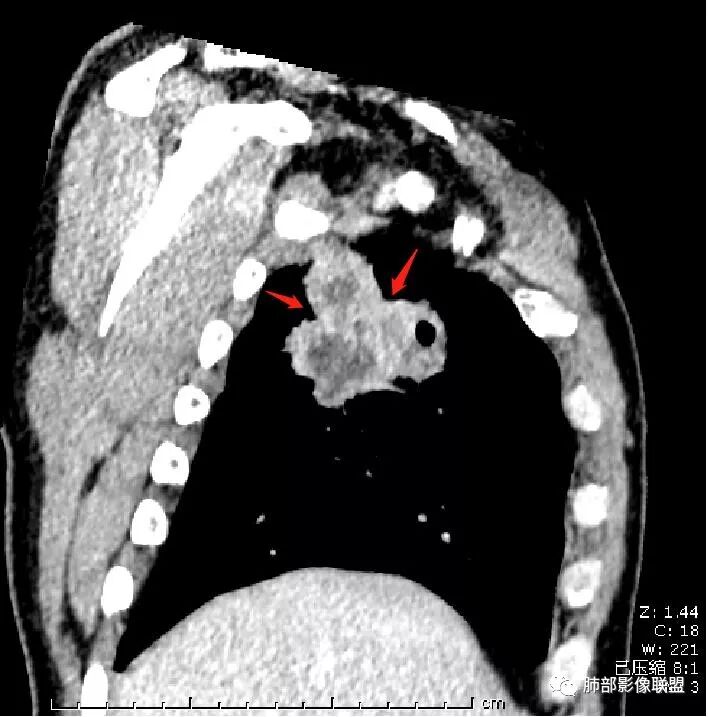

首先病灶示:跨尖、后、前三段,局部突入中叶;大家理解一下:是不是光滑的地方有叶裂,毛糙的地方没叶裂。

这个病变两侧受叶裂的局限,中央没有,如果是穿透叶裂的是否边缘也毛糙?事实上这叶裂边缘的叶裂是很光滑的,我倾向于这个是局部叶裂有缺陷;就是从缺陷处进来有病灶的本色:边缘毛糙;附近叶裂的阻挡,边缘光滑;既然怀疑是局部的缺陷就对良恶性没价值。

中央太突兀了,有道理;如果恶性侵犯也不会这么突兀,所以可能是有缺陷或薄弱的地方;

恶性侵犯,整体都会毛糙

对,这个病灶周围胸膜没有膨隆或占位效应,会不会病变以收缩为主;如果有缺陷,这种良恶性都可以,两侧胸膜没有膨隆,也不能说排除恶性;如果膨隆,恶性可能性大,但是也可以被阻挡。

第二种是局部叶裂畸形或发育不全、有缺陷,病灶经缺陷处侵犯蔓延,事实上叶裂缺并非少见,影像观察应当结合冠矢状位。

假如一个病灶直接跨越胸膜侵犯过来,应该边缘都很毛糙,不应该是最突出的地方毛糙,应该是逐步毛糙过去的,充其量越到外面毛糙越少;但事实上今天这个病变是一个很突兀的毛糙,突然间嘎然而止的毛糙;所以这个提示应该是从缺陷处跨过来的;还有今天的这个病例,病灶跨叶的部分对附近的胸膜是推移的,附近的胸膜还是很光滑,但是跨叶的病灶区很毛糙,提示跨叶部分存在胸膜缺陷可能;一般来说恶性肿瘤直接侵犯到对侧还是少的,如果这个地方你怀疑有缺陷,跨胸膜在诊断良恶性价值就不大了。